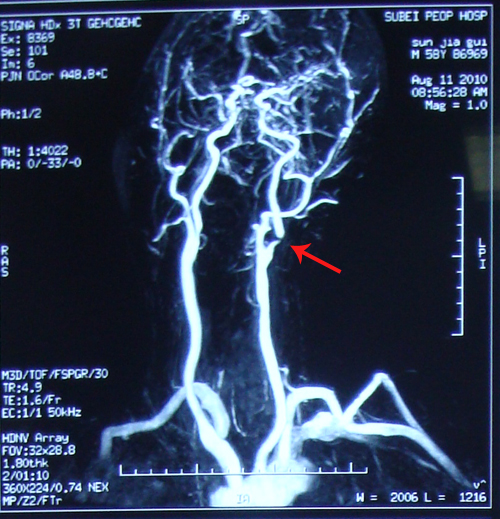

CEMRA:左侧大脑中动脉中段管腔,近端分支稀疏。

全脑血管造影:右侧大脑中动脉M1段完全闭塞,右侧大脑前以及大脑后动脉侧枝供应该区域。左侧颈内动脉起始段狭窄,最狭窄处达85%,左侧大脑后动脉部分交通支至左侧大脑中动脉供血区域其余血管未见明显异常。